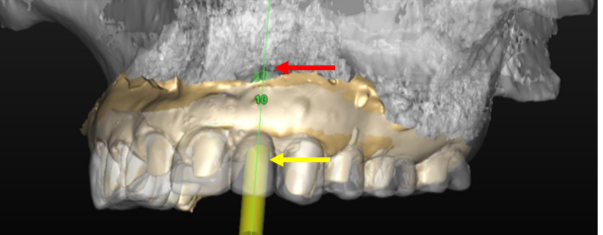

Precision Implant Placement always begins with meticulous planning using CBCT scans and dedicated implant‐planning software (Figs. 1-3). First, we virtually “insert” the implant on the CT scan so it centers beneath the future crown (Fig. 1). Then we design and fabricate a surgical guide (Fig. 2) to transfer that plan directly to the patient’s mouth. Finally, the guide seats on the patient’s teeth during surgery to ensure exact implant placement (Fig. 3), achieving both optimal bone support and prosthetic alignment.

Fig. 1: Virtual Implant Placement on the CT Scan Under the Temporary Crown